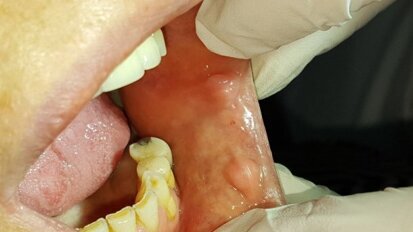

Zastosowanie lasera CO2 w leczeniu zmian na błonie śluzowej – opis przypadków

Lasery dużej mocy, w tym laser CO2, znajdują coraz szersze zastosowanie w stomatologii, w tym w chirurgii stomatologicznej.1 Ze względu na wysokie ...